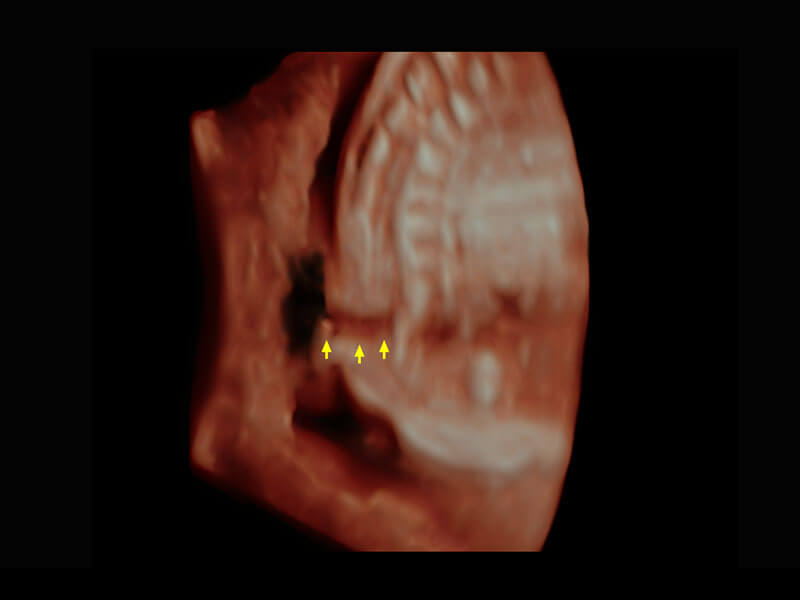

P60为盆底超声检查提供应用方案,多种腔内及腹部容积探头提供从二维、三维到四维的优异图像品质,实时快速三维容积数据获取,专业的测量工具包等人性化设计,为超声医生诊断提供有力保障。

能够简化盆底检查的操作流程,可在二维模式及三维成像模式下实现一键自动提取出标准切面、自动识别当前切面、自动测量,提升盆底检查的高效性,同时也能让青年医生快捷的获得准确的检查结果。